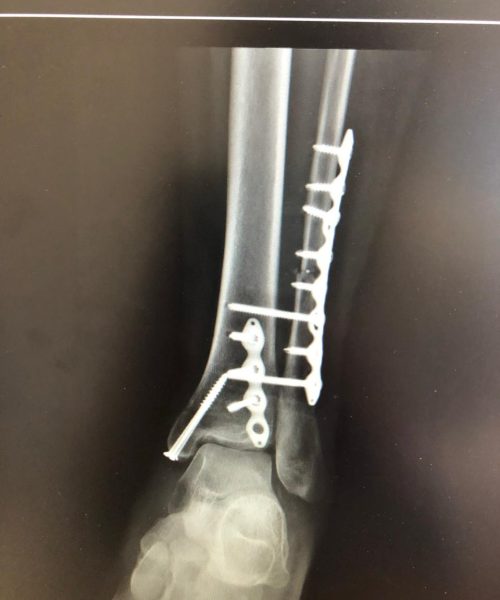

Fraturas no pé e tornozelo referem-se à quebra dos ossos nessas regiões, podendo ocorrer devido a traumas, quedas ou impactos.

Os tratamentos são indicados para pacientes com fraturas que podem variar de simples a complexas, comprometendo a função e a estabilidade.

O tratamento pode incluir imobilização com gesso, tala ou até mesmo cirurgia, dependendo da gravidade da fratura. A cirurgia pode envolver o uso de pinos, placas ou parafusos para fixar os ossos.

Riscos cirúrgicos incluem infecção, má cicatrização óssea e a necessidade de remoção posterior de hardware. O cirurgião deve discutir esses riscos detalhadamente com o paciente.

A recuperação pode variar significativamente, dependendo da gravidade da fratura e do tipo de tratamento. Geralmente, envolve um período de imobilização seguido por fisioterapia para restaurar a função e a mobilidade.